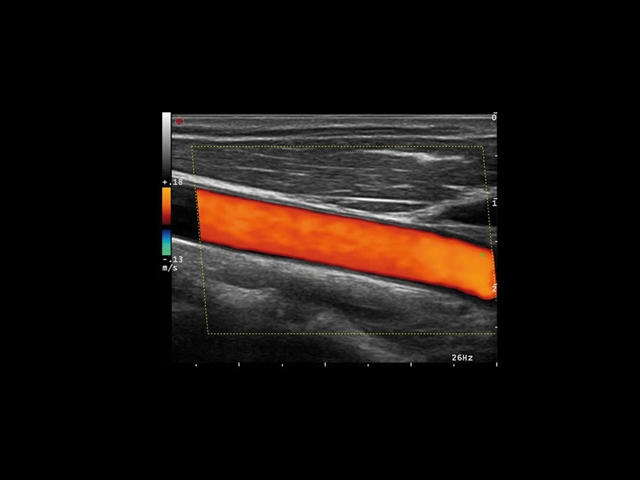

Сосудистая диагностика

Специализированные функции:

• Технология QIMT для точной оценки толщины интима-медиа

• QAS для качественной оценки артериальной жесткости

• XFlow Doppler с высокой чувствительностью к кровотоку

• Работа с контрастными веществами через технологию CnTI

Цветовой допплер:

Да